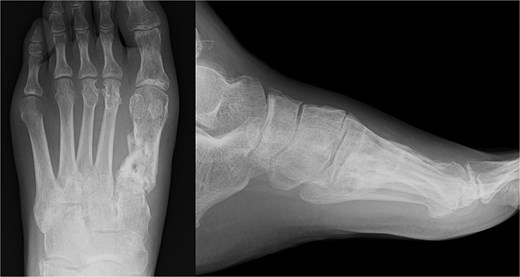

A 52-year-old man presented to our hospital with pain in the left ankle and forefoot after his left foot was caught in a wall while operating a tiller. Deformity was observed in the left ankle joint and the left forefoot. No evidence of neurovascular injuries or wounds was observed. The patient had a history of diabetes and hypertension. Radiography showed fractures of the left first metatarsal (Fig. 1a and b), tibial pylon, and distal fibula. Computed tomography (CT) revealed that the base of the first metatarsal was comminuted (Fig. 1c), and a dorsal skin prominence was identified due to a displaced dorsal fragment.

Radiography (a, b) and computed tomography (c) images of the left forefoot showing the comminuted first-metatarsal fracture.